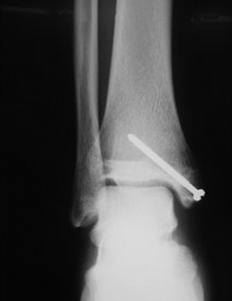

발의 관절이 안쪽으로 강하게 뒤틀어지면 발목과 연결된 거골에 밀려 내과골절이 발생할 수 있고, 뼈가 어긋남 없이 골절되었다면 깁스 등의 보존적 치료등을 하게 됩니다. 하지만, 골절부위가 어긋난 버린 상태라면 스크루핀 등으로 고정하는 수술을 할 가능성이 있습니다.

교통사고등에서 주로 보이는 골절입니다. 이 골절의 특징으로서 혈류장애에 의해 뼈의 괴사를 일으킬 수 있다고 알려져 있어 주의가 필요합니다. 골절부의 어긋남이 없다면 깁스 등의 보존적 치료로 가능하고, 어긋남이 있다면 스크루 등을 이용하여 수술을 할 가능성이 있습니다.